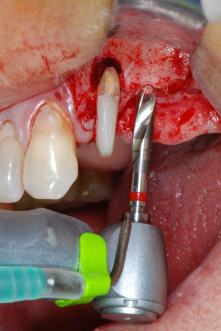

Zunächst wurde in einem Versuch, das Paro-Endo-Problem zu lösen, an der verbleibenden Wurzeloberfläche ein vorsichtiges Debridement mit einem piezochirurgischen Gerät vorgenommen (Piezomed, W&H) (Abb. 4); dann wurde der Apex mit dem gleichen Instrument im Sinne einer WSR abgetragen, um das verbleibende infizierte apikale Gewebe zu entfernen (Abb. 5). Eine retrograde Füllung war nicht notwendig, da die orthograde Füllung gerade revidiert worden war.

Im folgenden Schritt wurde das jeweilige Implantatbett an den Positionen 25 und 26 mit rotierenden Instrumenten in einem Winkelstück mit einem Übersetzungsverhältnis von 20:1 (WS-75 L G, W&H) und einem vor Kurzem aktualisierten leistungsstarken Implantatmotor präpariert (Implantmed, W&H) (Abb. 8 und 19).